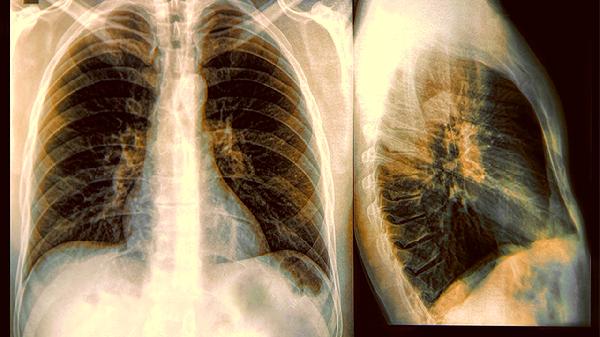

1、影像学上的朦胧美

磨玻璃结节在CT影像上呈现半透明状,就像隔着一层毛玻璃看东西。这种特殊表现源于肺泡内空气被部分替代,但尚未形成实体肿块。约20%的纯磨玻璃结节可能保持多年稳定,但混合型磨玻璃结节恶变风险显著升高。